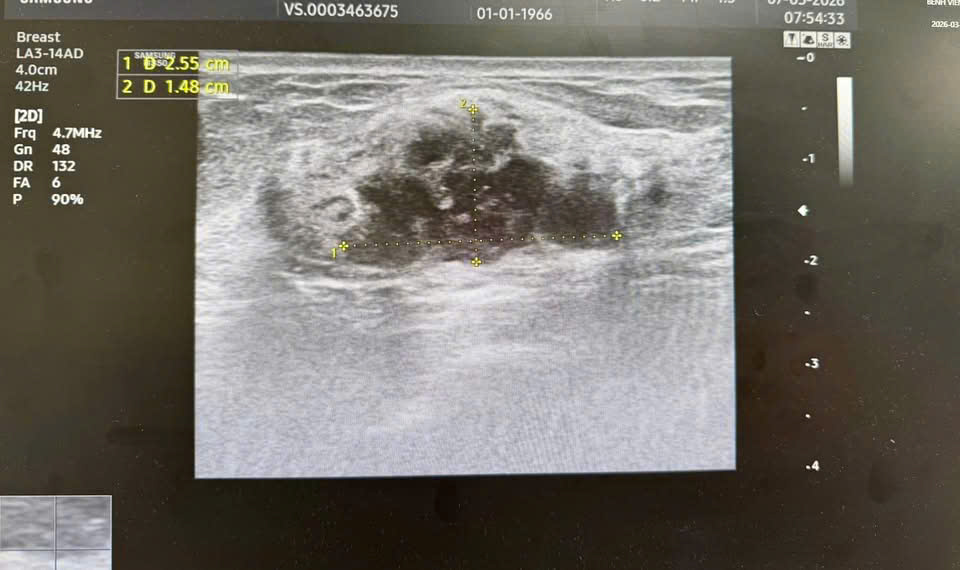

Hình ảnh khối u được phân loại BIRADS 4 trên siêu âm và chụp X-quang tuyến vú.

Kết quả siêu âm và chụp X-quang tuyến v:ú cho thấy hình ảnh khối u được phân loại BIRADS 4 – nhóm nghi ngờ ác tính cần làm thêm xét nghiệm. Sau đó, kết quả xét nghiệm tế bào học xác định bệnh nhân mắc UT biểu mô tuyến v:ú giai đoạn sớm.